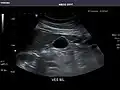

Abdominal Ultrasound (Full Exam)

STRUCTURED REPORT

(Technique: Transabdominal ultrasonography; Device: Toshiba Aplio XG)

Liver: Diffusely homogeneous and normal in echogenicity. No focal mass or contour nodularity. No intrahepatic biliary ductal dilatation.

Portal Vein: Patent main portal vein.

Gallbladder: No stones, wall thickening, or pericholecystic fluid.

Common Bile Duct: Nondilated measuring 1.3 mm at the level of the porta hepatis.

Pancreas: Visualized portions unremarkable.

Spleen: Normal in size.

Kidneys: Right and left kidneys measure 11.5 cm and 12 cm in length respectively. No hydronephrosis. Small left lower pole kidney cyst.

Ascites: None.

Aorta: Visualized portions normal in caliber, 16 x 15 mm.

IVC: Normal.

IMPRESSION:

Normal abdominal ultrasound.